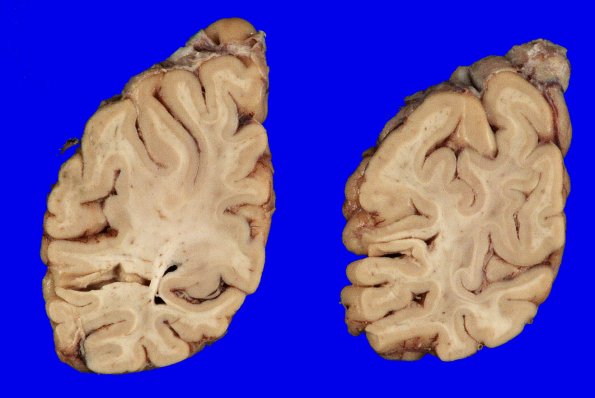

7A3 AGD (Case 7) Gross_3

There was mild atrophy in the more caudal brain regions.temporal and